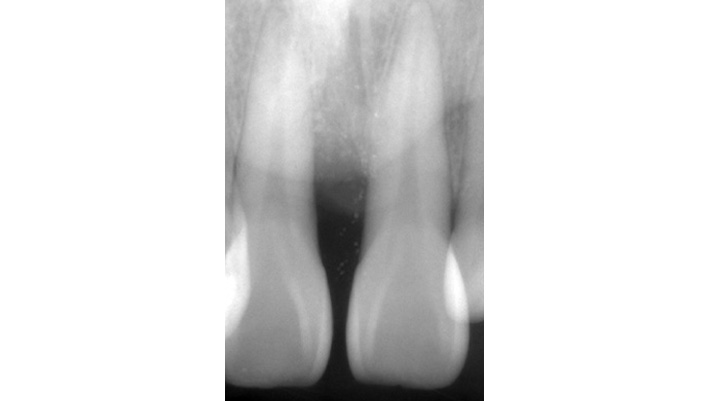

治療前

治療後

主訴 | 上の前歯がよく腫れる |

---|---|

治療期間 | 1~2ヶ月 |

治療費 | ¥77,000(税込) |

治療内容 | 歯周再生療法にて、歯周病で失った骨を再生しました。 |

治療のリスク | 100%成功するものではなく、適応出来ないケースもあります。 |